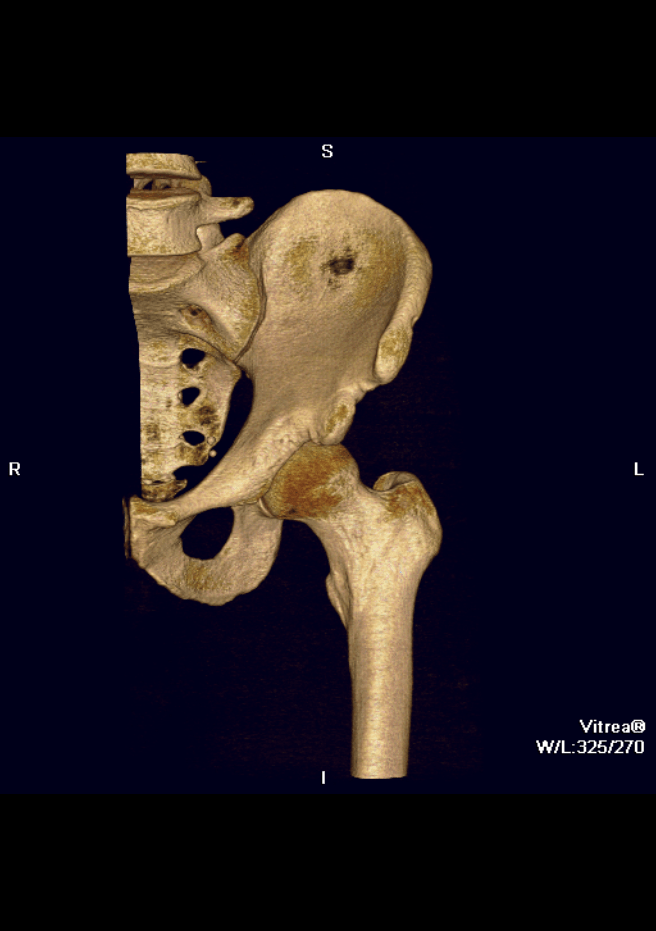

Dr Tim Dwyer is an orthopedic surgeon specializing in sports medicine and arthroscopy, performing surgery of the hip, knee and shoulder. Based at Women’s College and Mt Sinai Hospital, Dr Dwyer performs high volume ACL reconstruction, hip arthroscopy, rotator cuff repair, and operations for shoulder dislocation.